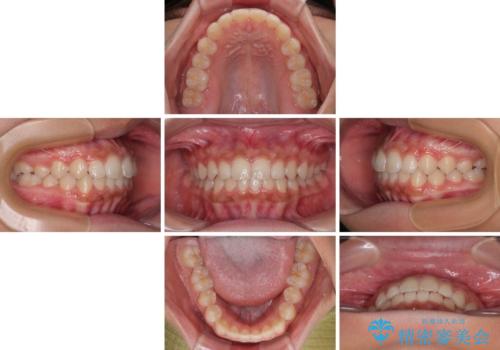

- 前歯の隙間を気にして来院された患者様です。

口元の突出感があり、小臼歯4本を抜歯して口元を引っ込める矯正治療も提案しましたが、本人は口元の突出感は気になっていないとのことで、インビザラインにて隙間やデコボコを改善することとしました。

軽度の歯列不正であったため、廉価版のインビザライン・モデレートパッケージにて治療を終えることができました。